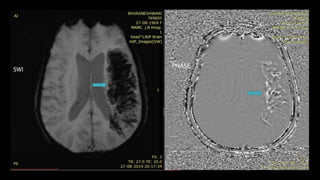

BLOOMING

hypointensity

Large infarcts may show –prominent hypointense

medullary veins

haemoglobin deoxygenation

HYPOINTENSI

TY

IN LEFT MCAARTERY SUSCEPTIBILTY

SIGN – MRI CORRELATE

OF HYPERDENSE

MCA SIGN ON NCCT

• #94 Extensive blooming is also seen within APPEARING white on phase images s/o large subacute infarct withj hemoorhagic transformation

• #96 These are the T1 post contrast axial images of a 75 year women with right sided weakness and left MCA terriortory infarct taken at DAY 0 , 2 AND DAY 7. Scan at D0 reveals mild intravascular enhancement , increasing on day 2 . Parenchymal enhancement is seen on day 7 scan .